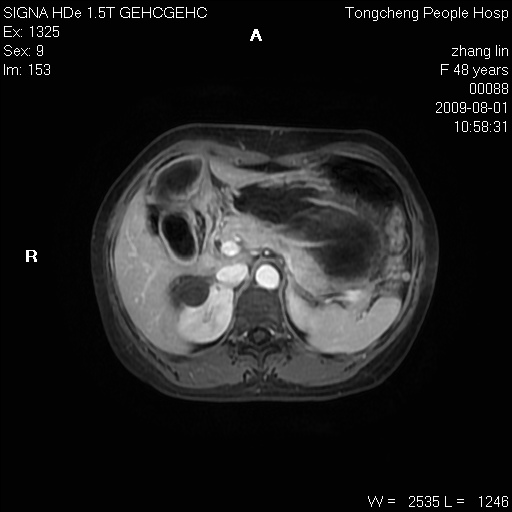

女,48岁。健康体检,彩超发现右肾占位性病变。平素健康。

临床诊断:右肾占位性病变,性质待定(囊肿?肿瘤?)。

上中腹部mr平扫+增强扫描,图像如下:

右肾上极见一类圆形病灶,t1wi呈等信号t2wi呈等高混杂信号,三期增强无强化,边界清---考虑囊肿出血。

同反相位均表现为等信号,病变无强化,考虑含蛋白的囊肿可能,弥散加权相或许有些帮助,

肝囊肿

慢性胆囊炎